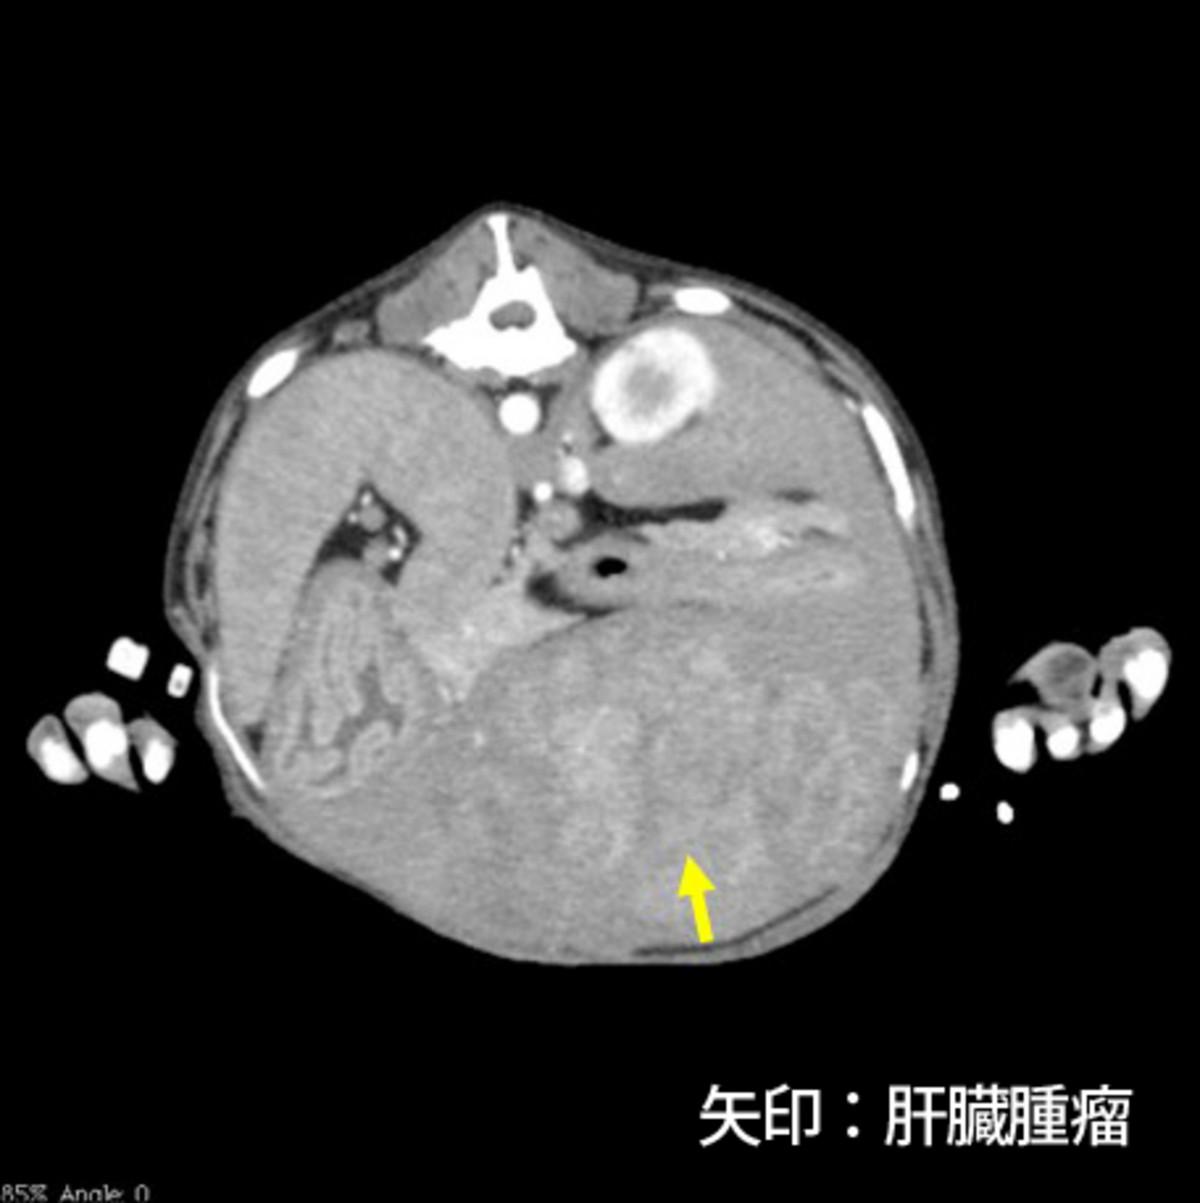

症例はバセンジー、去勢雄、11歳8ヵ月齢、10.5kgです。当院初診の一月前にふらつきを認め近医を受診し、低血糖(38mg/dL)、インスリン高値が認められたためインスリノーマと仮診断され、少量頻回の食事と糖液の投与により一般状態を維持していました。初診時の血液検査では血糖値は正常であり、CT検査にて膵臓右葉尾側に腫瘤(15×10×10mm)、肝臓外側左葉の腫瘤(5mm大×2)、肝門リンパ節腫大(12×10×6mm、15×9×7mm)が認められました(図1)。肝臓への転移が疑われるため、根治は難しい可能性が高いものの臨床症状およびQOLの改善を目的とした手術が予定されました。

図1.CT検査にて膵臓腫瘤(図1-1)、肝門リンパ節腫大(図1-2、1-3)を認めた